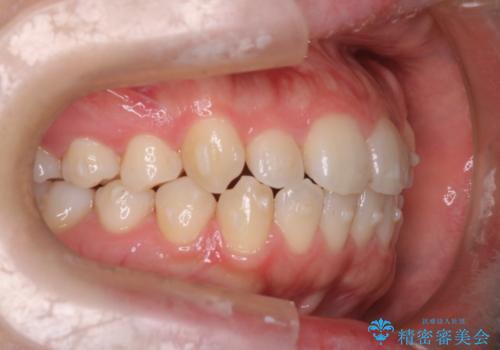

- 患者様は歯並びの乱れを気にされて来院されました。特に小臼歯の捻転(ねじれ)が強く、見た目だけでなく噛み合わせにも影響がありました。できるだけ目立たない方法を希望されていたため、インビザライン(マウスピース矯正)を基本としつつ、より精密な動きが必要な部分にはワイヤー矯正を併用する計画を立てました。また、小臼歯の捻転については**部分矯正(MTM:Minor Tooth Movement)**を取り入れ、効率的に改善を目指しました。

まず、全体の歯並びを整えるためにインビザラインを使用し、徐々に理想的な位置へと歯を移動させました。一方で、ねじれの強い小臼歯に対しては、**部分的なワイヤー矯正(MTM)**を行い、より精密なコントロールを実施。約2年の治療期間を経て、歯並びと噛み合わせが整い、見た目の美しさだけでなく、機能的な改善も達成しました。患者様からは「自然な仕上がりで、自信を持って笑えるようになった」と喜びの声をいただきました。